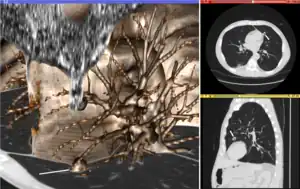

The figure "Visualization of Medical Imaging" illustrates several types of visualization: 1. the display of cross-sections as gray scale images; 2. reformatted views of gray scale images (the sagittal view in this example has a different orientation than the original direction of the image acquisition; and 3. A 3D volume rendering of the same data. The nodular lesion is clearly visible in the different presentations and has been annotated with a white line.